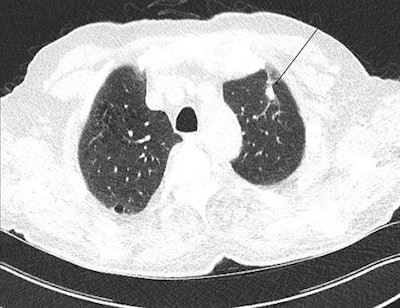

Arrow shows a benign nodule in the right lower lobe visualized on a low-dose screening CT. All images courtesy of Dr. Thomas Frauenfelder.CT screening has been implemented in North America but not in Europe, though a recent European position statement recommended that planning for the implementation of LDCT screening should start as soon as possible. Any related steps in Switzerland require careful preanalysis and caution, but the study team, led by research scientist Yuki Tomonaga from the Epidemiology, Biostatistics and Prevention Institute (EBPI) at the University of Zurich in Switzerland, hopes the work will help policymakers, payors, and guideline developers who face the decision of whether or not to implement LDCT screening.